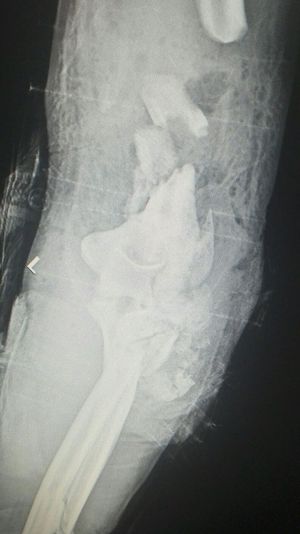

Accident

Fractures

Humerus

Elbow

Motorbike